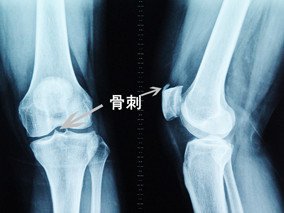

很多人因为膝关节疼痛而就诊,在医院的检查中会发现关节内长了骨刺,大家很迷惑的一个问题是:疼痛是骨刺引起的吗?去掉骨刺后我的关节是否就可以不疼痛了?

虽然骨刺是医生诊断骨性关节炎的一个依据,但绝大多数不是引起局部疼痛的真正原因,更不是它直接引起疼痛症状。只有当局部的骨刺对周围的软组织产生顶压等刺激时,才会引起局部的疼痛症状,并且这种情况非常少见。

导致关节疼痛的主要原因是关节软骨损伤、半月板磨损、关节力线改变等。因而相应的治疗需要在准确把握病因的基础上治疗才是正确的选择。

一般来讲,疼痛是由于关节内存在炎症,并非是存在的骨刺在起作用。所以单纯去掉骨刺并不能解决关节的疼痛问题,也不能解决关节炎问题。希望大家不要再轻信那些声称可以“消除骨刺”的药物或者可以“切除骨刺”的手术,这也是针对老年性退变性膝关节炎采用膝关节镜进行关节清理手术后效果不好的根本原因。